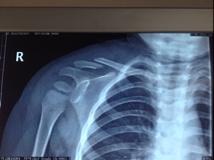

小儿锁骨骨折鼓包

小儿锁骨骨折鼓包,

小儿锁骨骨折

儿童锁骨骨折保守治疗12岁以下

锁骨骨折

锁骨骨折保守治疗